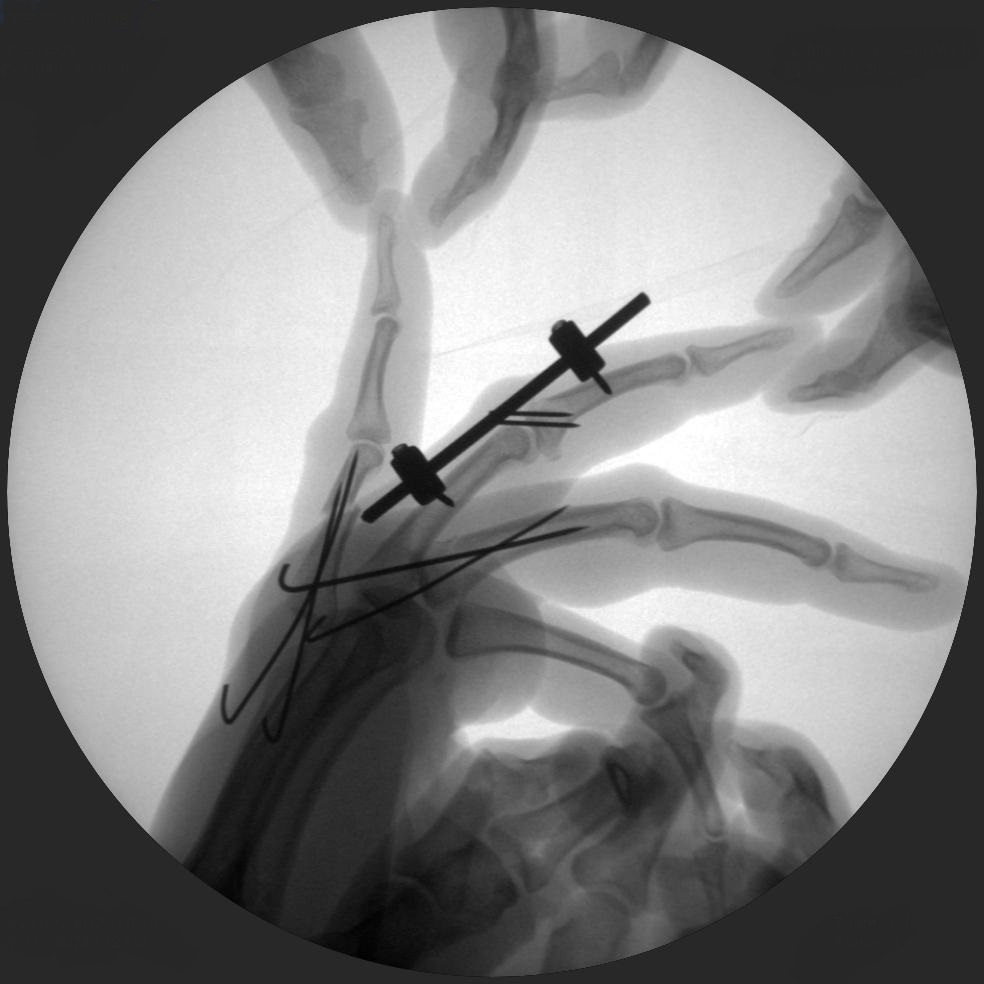

CRIF - Closed reduction internal fixation

ORIF - Open reduction internal fixation